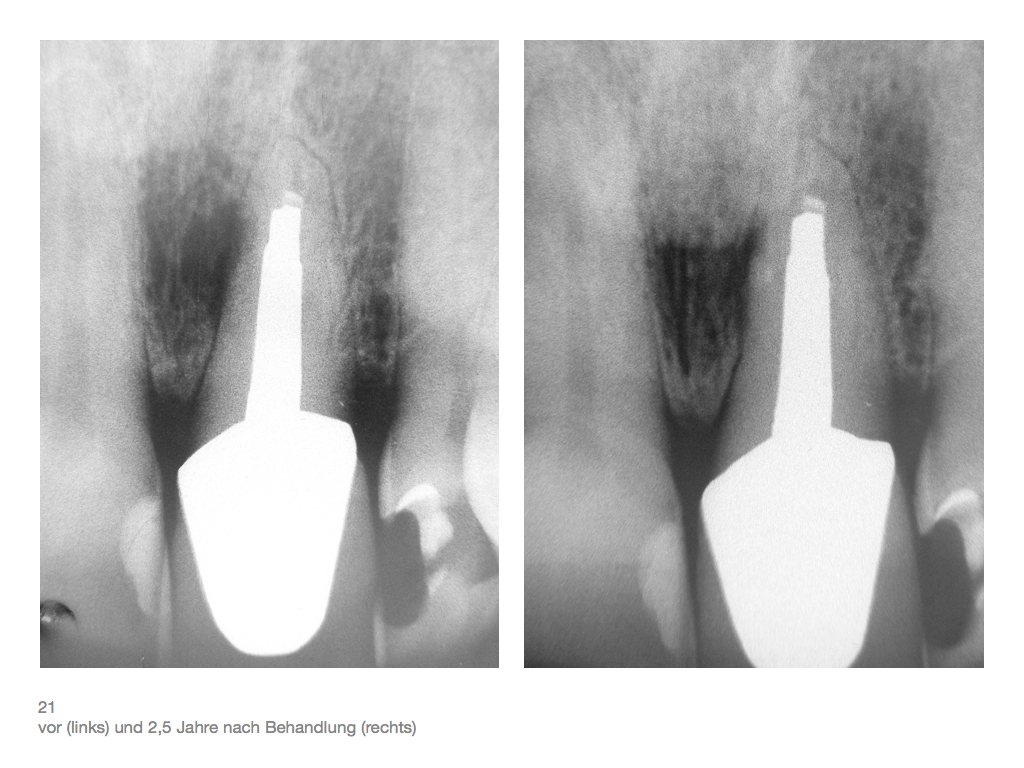

IF.028 Veröffentlicht 3. November 2012 am 1024 × 768 in Zahnerhalt „austherapierter“ Zähne durch endochirurgische Maßnahmen